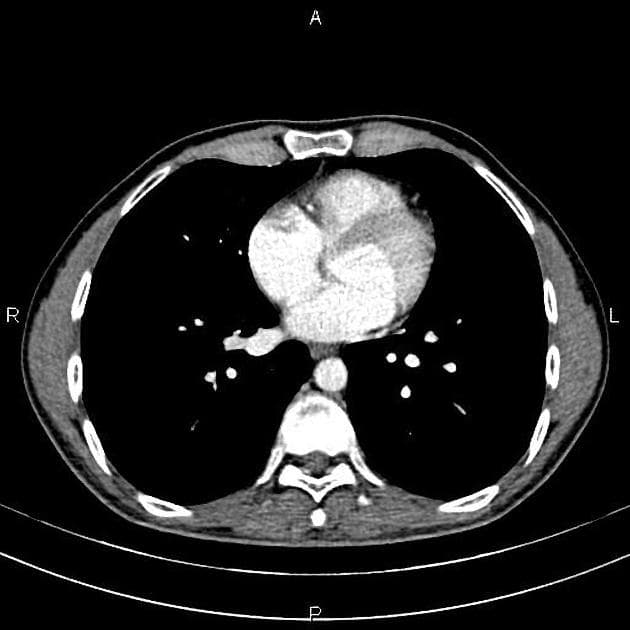

CT

CT gan đa thì là lý tưởng 4. Trên dãy không tiêm thuốc, tổn thương thường giảm tỷ trọng hoặc đồng tỷ trọng, nhưng có thể tăng tỷ trọng nếu nhu mô gan còn lại bị nhiễm mỡ. Sẹo trung tâm giảm tỷ trọng có thể thấy ở đến 60% các tổn thương có kích thước >3 cm 4.

Tăng sản mô đệm khu trú dạng nốt cho thấy ngấm thuốc động mạch rõ, đồng nhất, ngoại trừ sẹo trung tâm vẫn giảm tỷ trọng 4. Các động mạch trung tâm giãn to có thể thấy.

Ở thì tĩnh mạch cửa, tổn thương trở nên hơi tăng tỷ trọng hoặc đồng tỷ trọng so với gan và khó thấy rõ trong nhiều trường hợp, sẹo trung tâm vẫn giảm tỷ trọng. Tăng sản mô đệm khu trú dạng nốt nói chung không liên quan đến mỡ, vôi hóa hay xuất huyết.

Sẹo xơ cho thấy ngấm thuốc ở các pha trễ trong đến 80% các trường hợp 4.